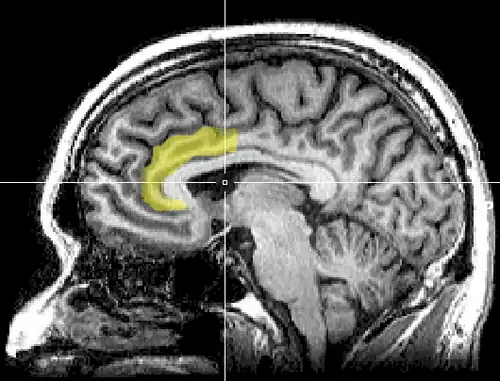

Anterior cingulate cortex

In human brains, the anterior cingulate cortex (ACC) is the frontal part of the cingulate cortex that resembles a "collar" surrounding the frontal part of the corpus callosum. It consists of Brodmann areas 24, 32, and 33.